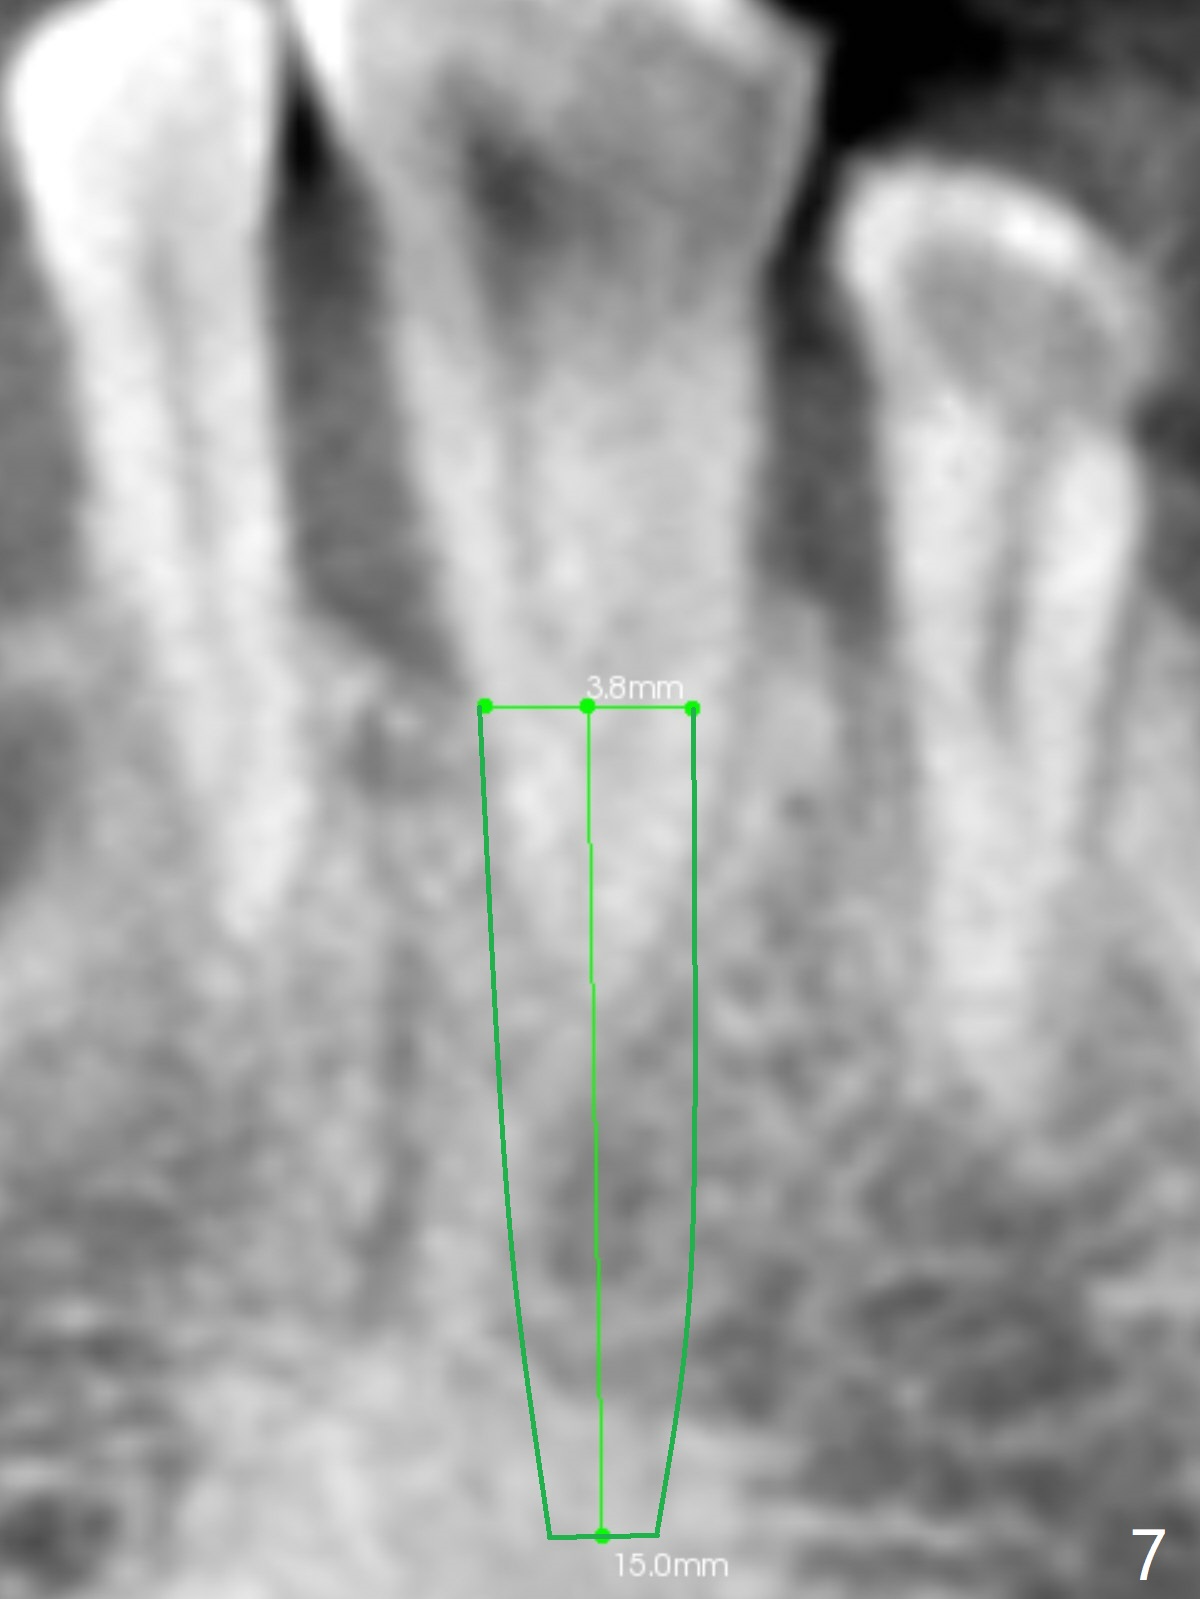

In fact, #22/23 mesiodistal width is ~ twice of that of an incisor (Fig.5). It is apparently more proper to place two smaller 1-piece implants (Fig.6) or a larger 2-piece one (Fig.7,8 (change to tissue-level one)).